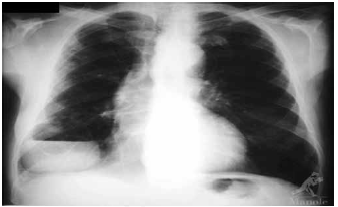

Paciente etilista, com dentes em mau estado de conservação, apresenta quadro de febre e tosse. O RX encontra-se a seguir. O tratamento mais indicado, nesse momento, é feito com